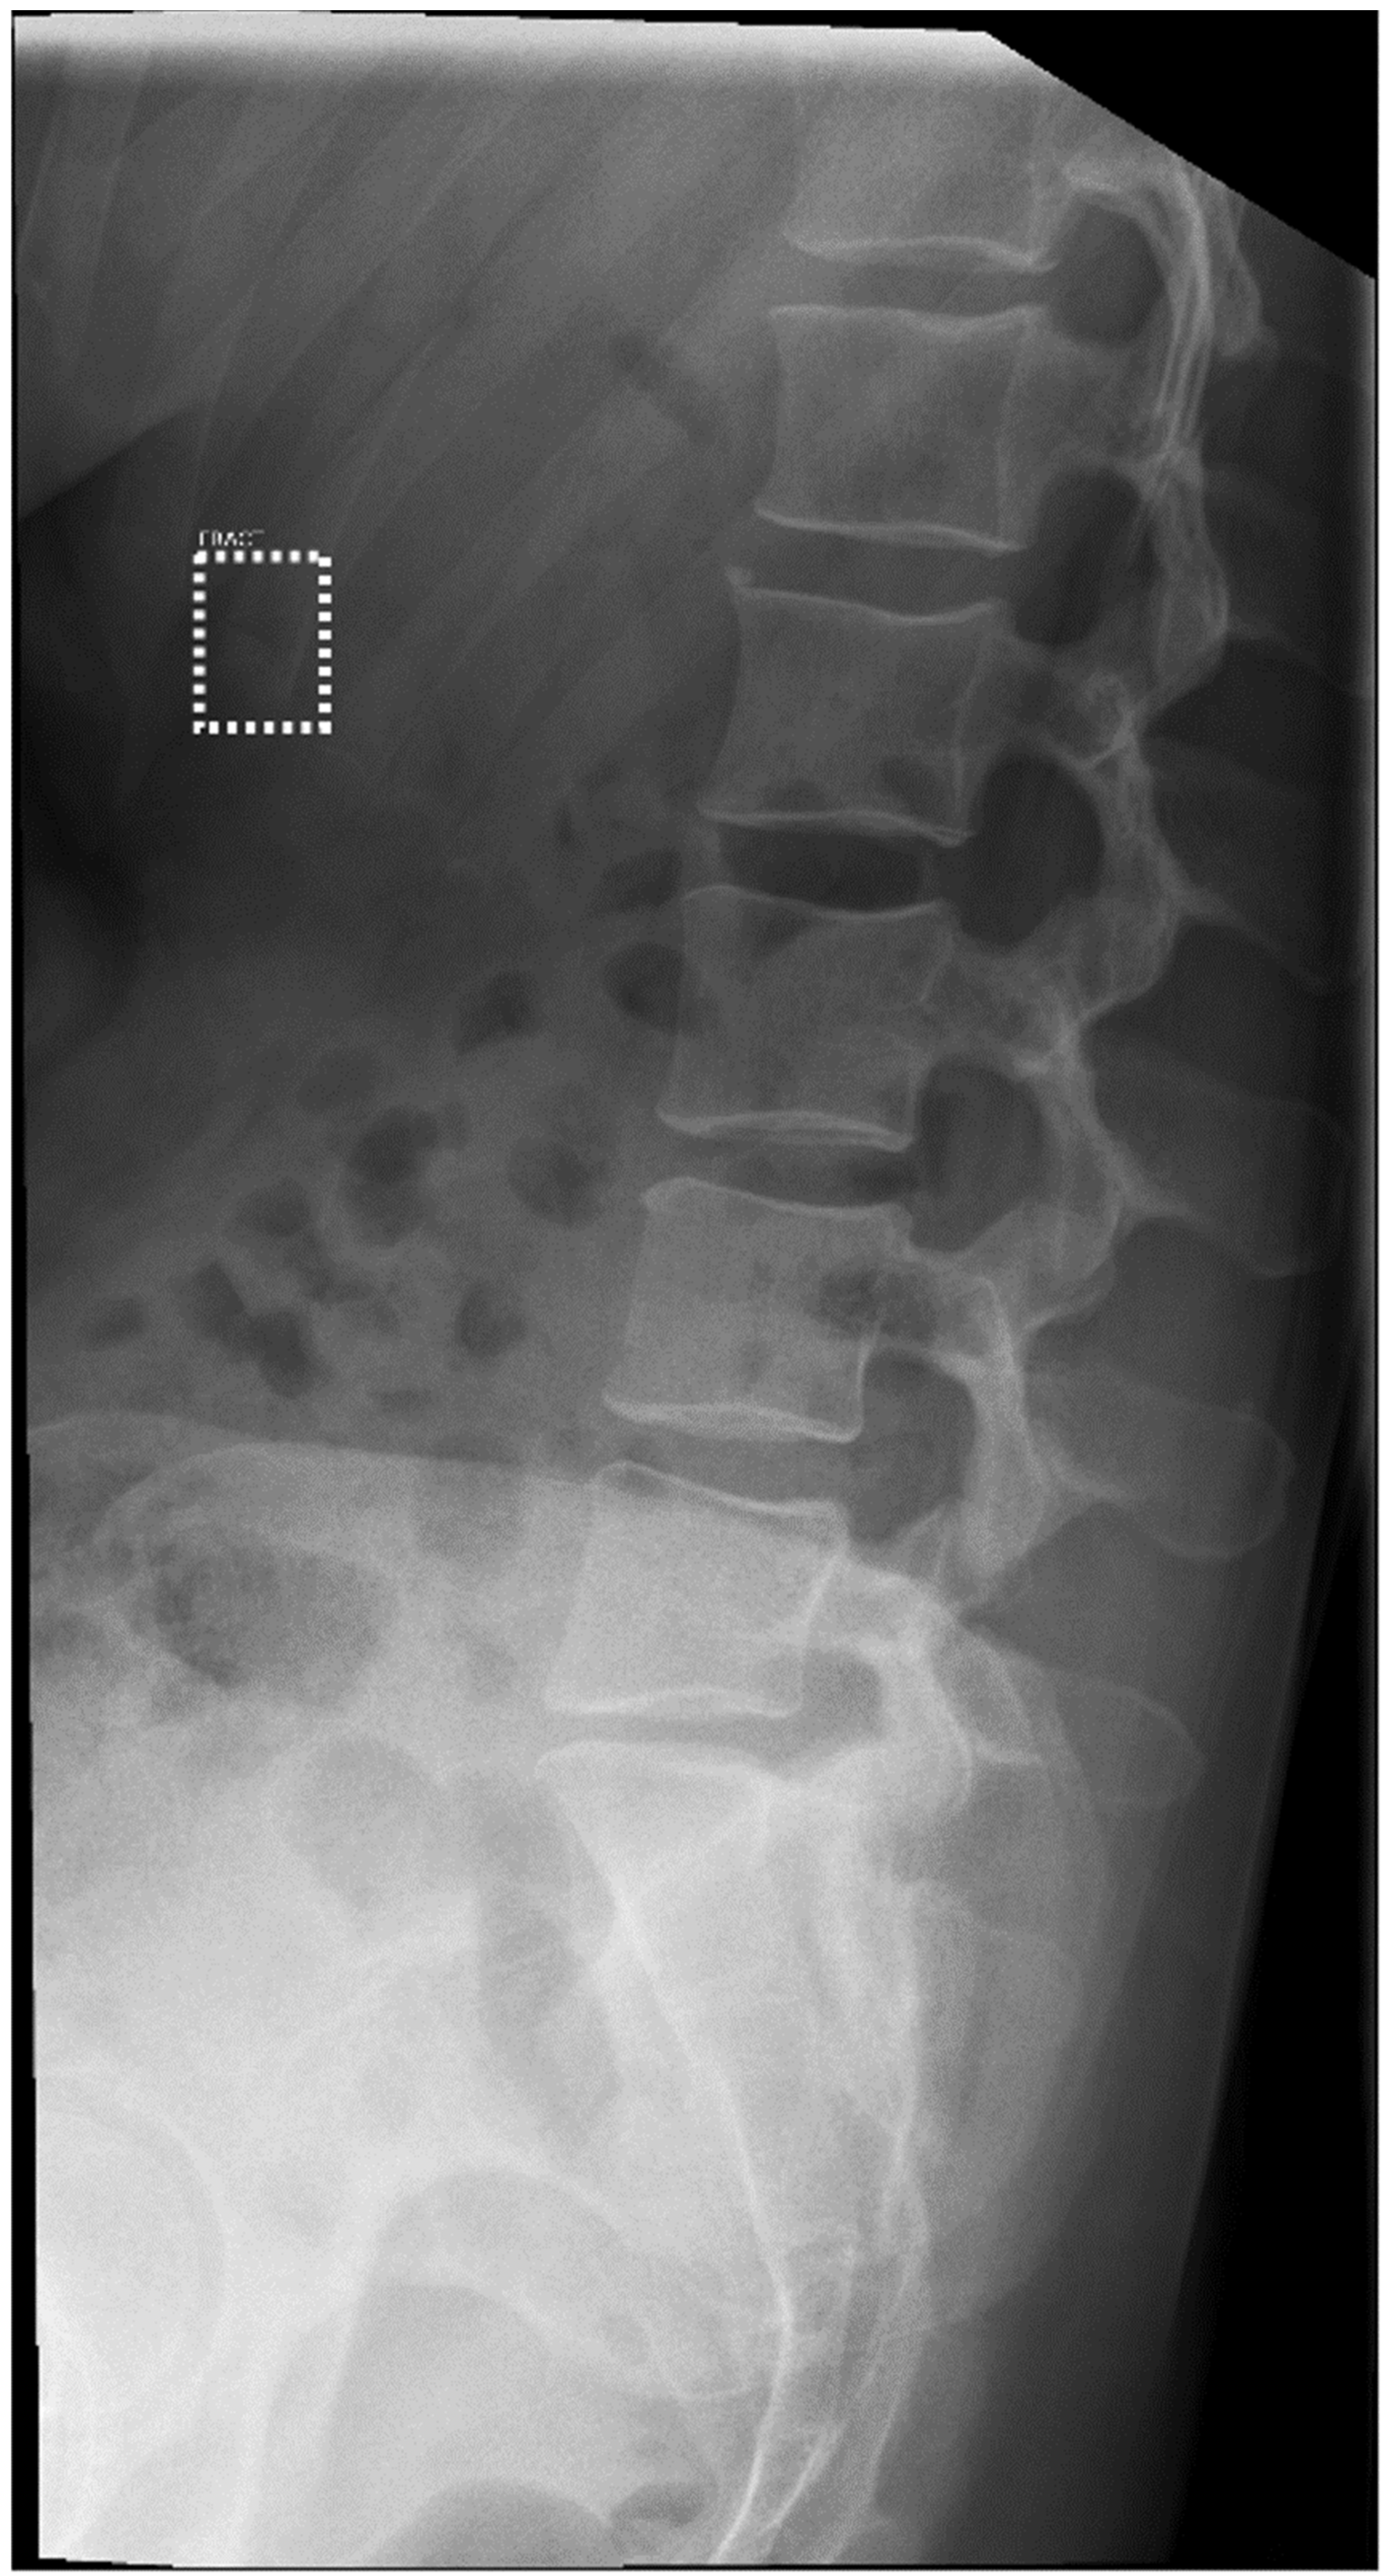

3.3. Sensitivity and Specificity by Anatomical Region